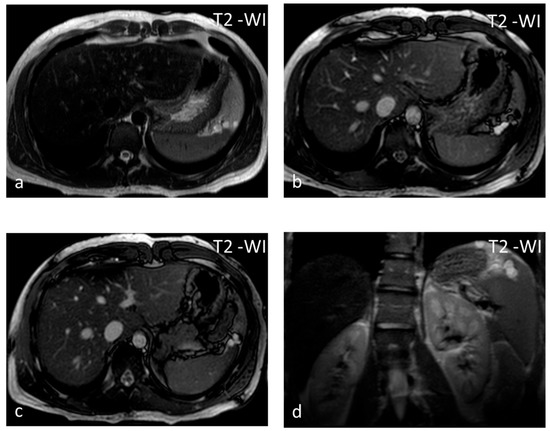

Figure 3.

Lymphangiomas. Multiple, subcapsular, hyperintense lesions, one of which appears multiloculated with thin septa, are seen on axial T2-WI images (a–c) and coronal plane T2-WI image (d).